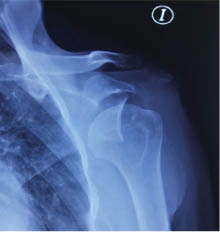

Plan: posterior al diagnóstico, se implementó protocolo preoperatorio y se realizó artroscopia de hombro izquierdo con reparación de Bankart y remplissage (Figura 4).

Se reportó en el citado paciente un resultado muy favorable posterior a la artroscopia de hombro con reparación de Bankart y remplissage, ya que se logró recuperar el déficit que presentaba el paciente al momento de evaluar los arcos de movilidad (extensión, abducción, flexión, rotación interna, rotación externa), así como la disminución del dolor.

Figura 4